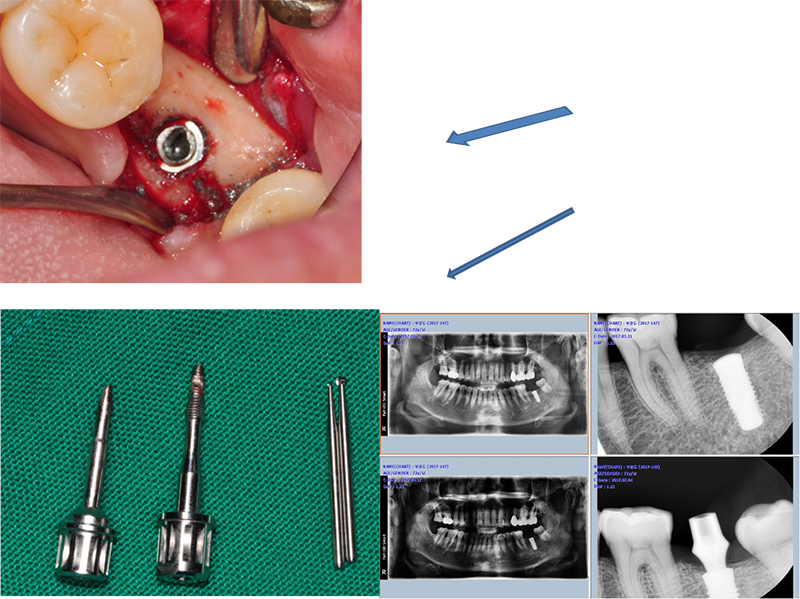

37¹ø 4.3 Á÷°æÀÇ ¿øÇöõÆ®

Á¦°ÅÇÏ´Ù°¡ ÈìÁýÀÌ ³¯ °Í °°¾Æ¼ Æ÷±âÇϰí

´ÙÀ½¿¡ ¾à¼Ó Àâ¾Ò´Âµ¥ ȯÀÚµµ Àúµµ ¹Ì·ç´Ù°¡ ÀÌ Áö°æµÊ.

ÆÄ³ë¶ó¸¶ »ó

°á±¹ ÇȽºÃÄ Á¦°Å

¾Æ¸¶µµ ±³ÇÕ¿¡ ¹®Á¦°¡ ÀÖ¾ú´ø µí

37¹ø abutment ÆÄÀý, µÚÂÊ¿¡ 8¹øÀÌ º¸À̰í, fixture Á÷°æÀÌ 5.0, Á¶±Ý ÈìÁýÀÌ ³ªµµ µÈ´Ù´Â »ý°¢À¸·Î Á¦°Å¼ö¼úÀ»

Çß´Ù.

3¹ø¿¡

³ª´²¼ °Ü¿ì Á¦°ÅÇÑ °æ¿ì